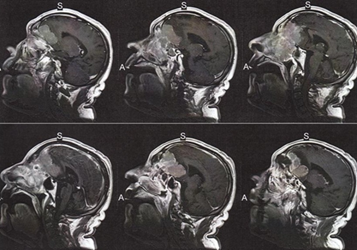

El paciente fue transferido al servicio 12 de Neurocirugía del Hospital Santo António dos Capuchos donde se realizaron pruebas de imagen (TAC) con las cuales se pudo identificar una deformación localizada en el etmoidal-nasal e intracraneal frontal extra axial, con disrupción de la pared inferior de la fosa nasal anterior, y con edema vasogénico cortical y subcortical no parénquima adyacente que contribuye al efecto de la masa tumoral (ver Figura 1), refiriéndose en el reporte radiológico que se podría tratar de un posible estesioneuroblastoma, que posteriormente fue confirmado a través de citología (biopsia). Una semana después de su internamiento el paciente presentó un cuadro de desinhibición conductual por afectación tumoral en el área de la corteza prefrontal (ver Figura 2).

Figura 1. Estudio de resonancia magnética-secuencia 3D-lateral

Nota: En las imágenes se pueden observar las dimensiones del tumor que se inicia en las fosas nasales y crece hasta la corteza prefrontal afectando la región orbitofrontal.